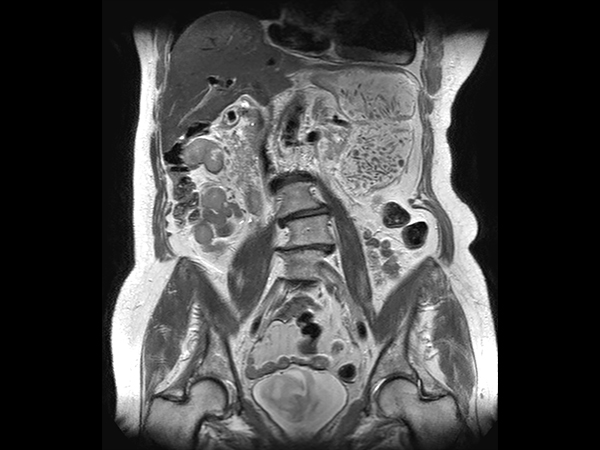

Coronal T2w TSE dS SENSE = 5, MobiView